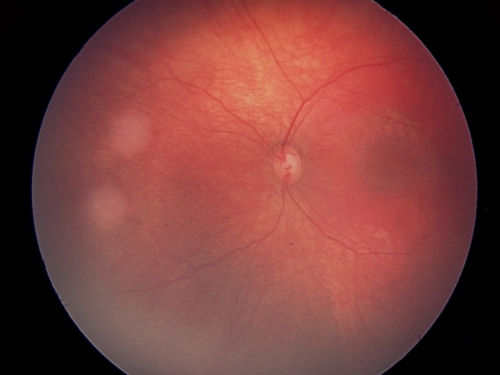

This is an EUA picture of retinoblastoma tumor group B. Tumor group B has low risk of losing the eye. Group B includes a larger tumor that is located near important structures.

Tumor Group B

The tumor is larger and/or near important eye structures.